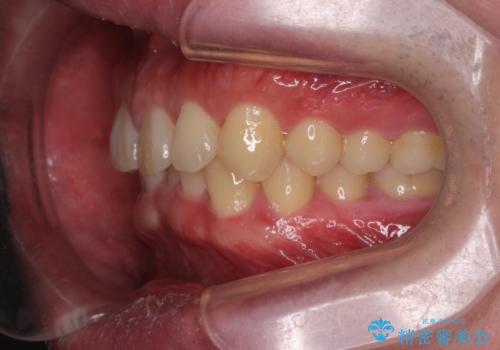

下の歯のがたつきが気になる。 インビザラン&ワイヤー部分矯正併用

- 下の歯が気になるとの事で来院。

左上の奥歯がシザーバイトがありワイヤーで部分的な矯正を行い、シザーバイトを改善した後にインビザラインで全体的な矯正治療を行いました。

シザーバイトは歯と歯が噛み合っていないのでしっかり噛むように処置をする必要があります。

歯のがたつきが改善され大変満足されました。